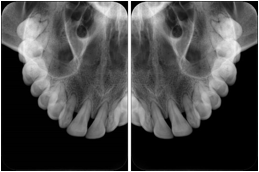

Intra-oral radiography typically involves acquisition of multiple images of various parts of the dentition. Many digital radiographic systems offer customized templates that are used for displaying the images in a study on the screen. These templates may also be referred to as mounts or view sets. The Structured Display Object represents a standard method of encoding and exchanging the layout and intended display of Structured Displays. A structured display object created in this manner could be stored with a study and exchanged with images to allow for complete reproduction of the original exam.

1. A patient visits a General Dentist where a Full Mouth Series Exam with 18 images is acquired. The dentist observes severe bone loss and refers the patient to a Periodontist. The 18 images from the Full Mouth Series along with a Structured Display are copied to a DICOM Interchange CD and sent with the patient to see the specialist. The Periodontist uses the CD to open the exam in his Dental Radiographic Software and consults via phone with the General Dentist. Both are able to observe the same exam showing the images on each user's display using the exact same layout.

Intra-oral Full Mouth Series Structured Display

Figure OO-1. Intra-oral Full Mouth Series Structured Display